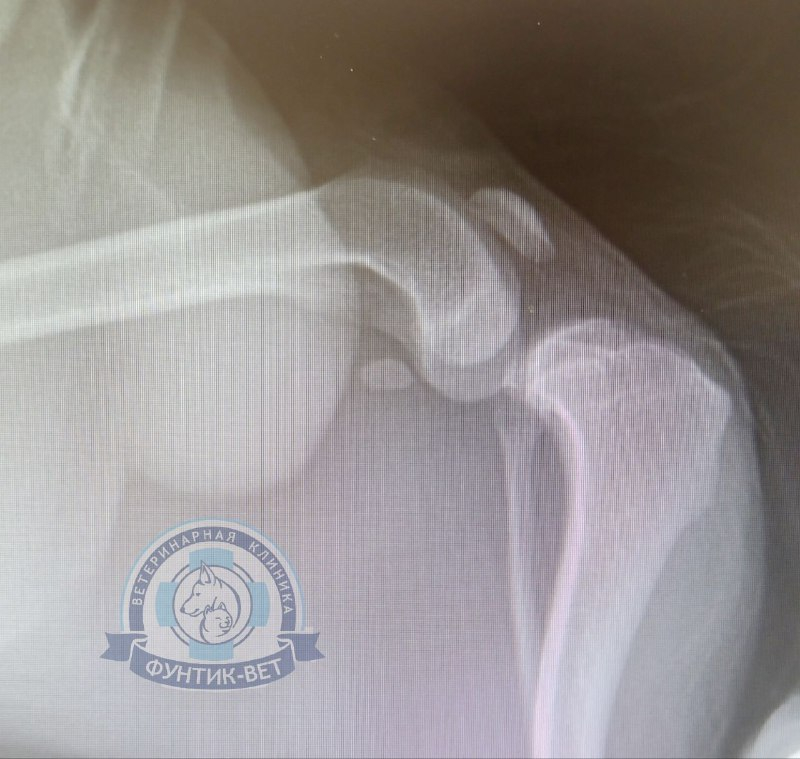

3. Рентгенография.